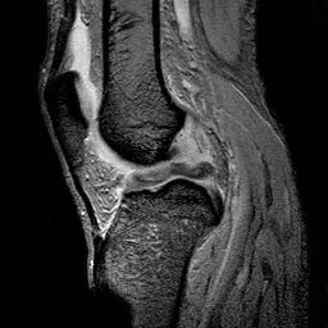

1、水平撕裂

2、较少见3、III级高信号与胫骨平台平行,到达半月板的游离缘或一侧关节面

(半月板水平撕裂)